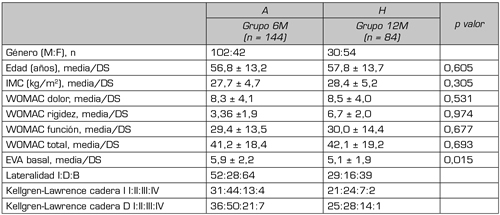

No hubo distinciones significativas entre los dos grupos con respecto a la demografía o a los valores basales de los cuestionarios de referencia (Tabla II), con la salvedad de la EVA que mostraba una diferencia de 0,8 puntos con una p = 0,015. No obstante, dado que de manera estandarizada se considera que en la medición del dolor con la escala EVA, debe producirse un cambio de al menos dos puntos para considerarse significativo, esta diferencia tiene un valor relativo. Los resultados intragrupo en relación con la evolución de los pacientes desde el inicio del tratamiento se muestran en la Tabla III. Se observa que el grupo A6M, que recibió una infiltración con A y volvió a la consulta 6 meses después, mostró mejoras significativas en relación con la disminución del dolor en la cadera medida tanto con la EVA (p < 0,001) como con el WOMAC dolor (p = 0,003), así como en el resultado del índice WOMAC global (p = 0,027). Sin embargo, no se produjeron cambios estadísticamente relevantes en el apartado de la rigidez y de la función medidos con el WOMAC. En lo que se refiere al grupo H12M, evaluado al año de la infiltración mostró mejora significativa en todos los parámetros registrados. Tanto la EVA (p < 0,001) como el WOMAC global (p = 0,010) y sus diferentes dimensiones registraron mejorías significativas. Es relevante el resultado del valor WOMAC rigidez que a los 12 meses mostró una mejora significativa importante (p < 0,001) y en menor medida el WOMAC función (p = 0,018).

Tabla II. Características basales de los pacientes incluidos en este estudio.

6M: 6 meses de seguimiento tras infiltración única con A. 12M: 12 meses de seguimiento tras infiltración única con H. EVA: escala analógica visual. WOMAC: Western Ontario and McMaster Universities Ostearthritis Index. Datos proporcionados como media ± DS (desviación estándar), o valores absolutos. El valor p fue calculado con un valor alfa establecido en 0,05 como significativo. I: izquierda. D: derecha. B. bilateral.